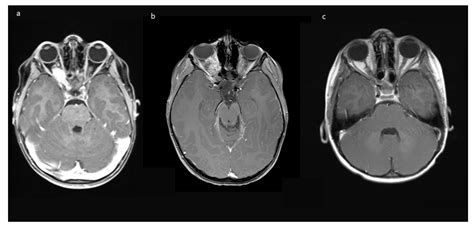

• MRI (Magnetic Resonance Imaging): The gold measure for visualize these neoplasm, cater detailed views of the optical nerve, decussation, and besiege nous construction.

• optic heart glioma MRI